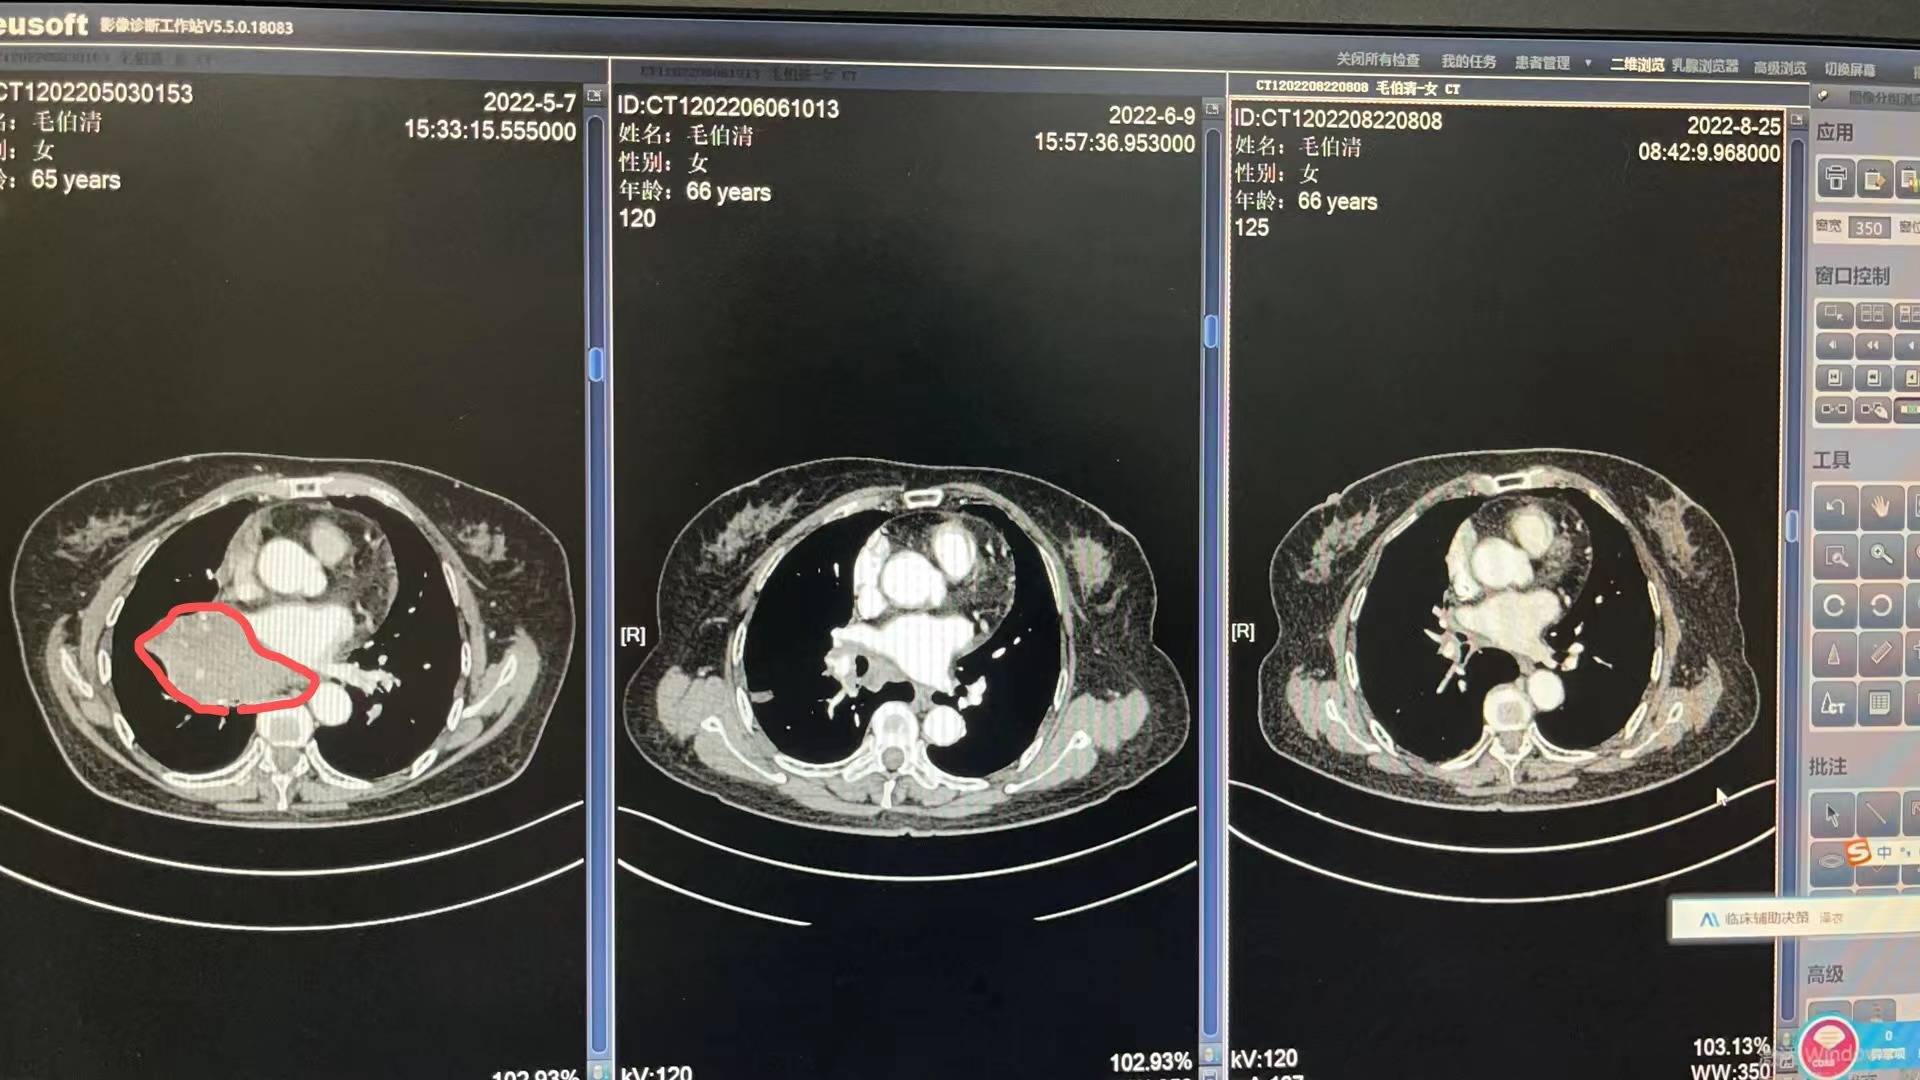

5月3号妈妈入院开始各种检查流程,5月13号病理出来,没有逃过此劫,确诊小细胞肺癌T4N2M0 IIIc期 局限期。妈妈的肿瘤是比较大的,5月14号上治疗,依托铂苷+顺铂,第二次化疗是6月6号,第三次化疗是6月29号,都是化疗三天出院,打升白针,便秘严重,喝乳果糖没啥用,两三天后自然好转。医生开了中药饮片以及一些药出院,刚化疗完那几天妈妈状态很不好,没力气,没精神,喜安静,但是可以下床吃饭,大部分时间躺床上睡觉。食欲不是很好,给她熬的瘦肉粥。四五天后状态开始慢慢好转!7月11号开始放疗,期间停掉第四次化疗,医生说怕身体承受不住,我妈是1天2次,15天完成,20次放疗后出现吞咽有哽咽感,医生只开了一瓶康复新液,就没喝了,7月底放疗结束后,慢慢哽咽感减退,医生让我妈妈回家休息一个把月。

每次她的血常规和肝肾功能都比较不错,有一点贫血的迹象,医生让吃点猪肝和血旺!她的白细胞和血小板都在往下掉,虽然都还在正常值范围内,医生说不错,可是我有一些些紧张!因为妈妈还有三次化疗。前天我妈妈去做了一个胸部复查,她的肿瘤基本没有了,其实在她第二次化疗后复查,肿瘤就小了很多,这次结果医生说还有些残留。准备这次入院化疗给她做一个胸部pet,看看残留的性质是不是活性,如果不是,就表示影像完全没有了。

附上医生给我截图的影像图和复查报告,请比我懂得多,比我专业的朋友帮忙看看!